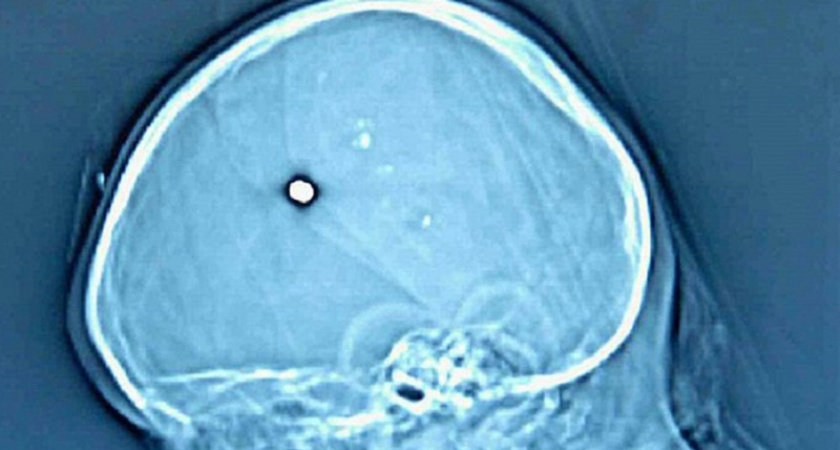

Житель Брянской области Александр 19 лет от роду обратился в поликлинику с сильной головной болью – врачи обнаружили, что он натурально ходит с пулей в голове. Причём, как, выяснилось, уже пять лет, пишет Baza. Когда Саше было 14 лет, он вместе со старшим братом Никитой гостил у бабушки. Как-то парни решили пострелять из пневматической винтовки, и одна пуля, срикошетив, попала Саше в голову. Родители узнали об этом тогда же, но мальчик уверил, что у него ничего не болит, поэтому идти к врачам не нужно. Теперь под Новый год голова Александра напомнила ему, что в ней уже несколько лет находится пуля. У него разболелась голова, он пришёл в местную поликлинику, затем его отправили в областную больницу, где врачи диагностировали у него инородное тело в правой теменной области и подострую гематому в правом полушарии. Его жизни ничего не угрожает, пулю скоро вытащат. #bryakingnews Подписывайтесь на наш уютный Telegram-канал «Брянск.Ньюс», группу «ВКонтакте» «Брянск | News» - ссылки на самые интересные новости и значимые репосты